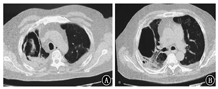

患者短期内双肺出现散在斑片影及斑点影,伴大小不等空洞,考虑肺部感染性疾病。入院后给予比阿培南(0.6 g,静脉滴注,2次/d)+万古霉素(0.5 g,静脉滴注,每8小时1次)联合抗细菌,继续醋酸泼尼松40 mg/d口服抗炎,并给予多索茶碱静脉滴注、雾化吸入布地奈德及特布他林平喘,氨溴索静脉滴注化痰,皮下注射胰岛素控制血糖等治疗。完善相关检查,ESR为47 mm/h;C反应蛋白96.10 mg/L;生化:钾4.0 mmol/L,钠131.0 mmol/L,氯96.0 mmol/L,空腹血糖17.0 mmol/L,尿素7.1 mmol/L,肌酐68.0 μmol/L,丙氨酸氨基转移酶29.0 U/L,天门冬氨酸氨基转移酶13.0 U/L,乳酸脱氢酶253 U/L,肌酸激酶79 U/L,总蛋白51.1 g/L,白蛋白30.8 g/L。尿常规:葡萄糖++++;血结核菌38kD蛋白阴性,结核菌外膜抗体阳性;结核菌素试验阴性;降钙素原、抗链球菌O、类风湿因子、自身抗体系列、肿瘤相关抗原系列、粪常规均正常。术前四项(乙肝表面抗原、丙肝抗体、人类免疫缺陷病毒抗体、梅毒血清特异性抗体)阴性。心电图大致正常。心脏超声:主动脉瓣钙化,左室后壁运动幅度稍减低,左室舒张功能减低。腹部超声:脂肪肝,余未见异常。肺功能:第1秒用力呼气容积/FVC为43.22%,第1秒用力呼气容积占预计值百分比为24.9%,提示阻塞性通气功能障碍,小气道功能障碍,残气量/肺总量轻度增高,弥散功能重度减低。痰涂片找抗酸杆菌阴性(3次)。患者入院当日(2018年1月26日)发热,最高体温达38 ℃;1月27日体温正常;1月28日再次发热,最高体温达38.1 ℃;1月29日之后未再发热,憋喘较前略好转,痰中带血减少。1月29日痰涂片:革兰阳性球菌可见;痰真菌培养:白色假丝酵母菌+。1月30日血1,3-β-D葡聚糖检测(G试验):247.3 μg/L(升高);血常规:白细胞计数12.56×109/L,红细胞计数5.00×1012/L,血红蛋白143 g/L,血小板计数179×109/L,中性粒细胞比例85.3%,淋巴细胞比例7.6%;C反应蛋白55.10 mg/L;血气分析:pH值7.43,PaCO2为48.4 mmHg,PaO2为81.6 mmHg,SaO2为95.8%。入院后每日皮下注射胰岛素累积剂量56 IU。1月26日至1月30日血糖控制不理想,空腹血糖波动于11~18 mmol/L,早餐及午餐后2 h血糖波动于10~18 mmol/L,晚餐后2 h血糖波动于15~21 mmol/L。患者痰检见白色假丝酵母菌+,G试验轻度增高(近期有应用哌拉西林舒巴坦钠史,不排除干扰),近期有糖皮质激素应用史,血糖控制欠佳,综合以上因素,考虑肺真菌感染不排除。1月30日给予伏立康唑200 mg口服抗真菌,每12小时1次(第1个24小时400 mg/次),同时减量醋酸泼尼松为30 mg/d。2月2日痰真菌培养:曲霉菌属+(2次),白色假丝酵母菌+,进一步支持真菌感染,建议行气管镜检查,患者因喘憋不适,一直不同意。之后又有2次痰培养:曲霉菌属1~2个菌落。2月5日患者憋喘较重,复查血常规:白细胞计数23.32×109/L,红细胞计数5.22×1012/L,血红蛋白151 g/L,血小板计数208×109/L,中性粒细胞比例92.2%,淋巴细胞比例3.7%;C反应蛋白229.80 mg/L;血气分析:pH值7.44,PaCO2为47.3 mmHg,PaO2为82.3 mmHg,SaO2为95.7%,提示感染加重。2月5日伏立康唑改为0.3 g,静脉滴注,每12小时1次。2月6日胸部CT示双肺散在斑片影及斑点影,伴大小不等空洞,与1月26日胸部CT比较右肺上叶空洞增大,右肺上叶病变进展(图3)。继续伏立康唑静脉滴注抗真菌,比阿培南联合万古霉素抗细菌治疗。2月12日胸部CT示右肺上叶空洞较2月6日进一步增大(图4)。2月12日血气分析:pH值7.45,PaCO2为57.2 mmHg,PaO2为78.3 mmHg,SaO2为95.1%。经反复动员,2月13日患者同意气管镜检查,结果(图5)示主气管黏膜表面可见白色分泌物附着;左上叶支气管黏膜充血明显,可见大量脓性分泌物;右上叶支气管各叶段开口变窄,以右上叶尖段开口变窄明显;右上叶支气管黏膜充血水肿明显,活检或刷检易出血。气管镜刷片及灌洗液病理见少许坏死物及中性粒细胞,未见肿瘤细胞。支气管镜肺活检(右上叶)病理:送检肺组织慢性炎,肺间质可见单核细胞浸润,纤维组织增生,肺泡上皮增生,肺组织表面附着成团的坏死物,坏死物中可见真菌菌丝及孢子。气管镜刷片培养:曲霉菌属1个菌落;气管镜后痰培养:曲霉菌属4个菌落。患者IPA诊断依据充足,应用伏立康唑效果差,2月14日改为两性霉素B脂质体静脉滴注,从10 mg/d始,逐日递增,增至150 mg/d时患者精神萎靡、憋喘、乏力、纳差、尿少、肾功能异常,尿素18.5 mmol/L,肌酐166 μmol/L,总蛋白45.6 g/L,白蛋白26.9 g/L。2月18日血气分析:pH值7.38,PaCO2为55.4 mmHg,PaO2为72.4 mmHg,SaO2为93.5%。考虑患者对该药不良反应较大,停用两性霉素B脂质体。2月19日给予伏立康唑(0.3 g,静脉滴注,每12小时1次)联合卡泊芬净(50 mg/d,静脉滴注)抗曲霉菌治疗。2月20日后患者多次血气分析示PaCO2升高,波动于56~79 mmHg,PaO2低,波动于50~80 mmHg,给予保肾、人血白蛋白支持、无创呼吸机辅助通气等治疗。口服泼尼松经逐渐减量,于2月17日后停用。住院期间患者一直纳差,进食量少,尽管每日皮下注射胰岛素累积剂量60 IU,但血糖仍控制不理想,空腹血糖波动于12~20 mmol/L,餐后2 h血糖波动于14~26 mmol/L;自停用泼尼松后,血糖逐渐好转,空腹血糖波动于8~10 mmol/L,餐后2 h血糖波动于11~14 mmol/L。3月6日血气分析:pH值7.35,PaCO2为55.4 mmHg,PaO2为72.4 mmHg,SaO2为93.5%。3月6日胸部CT示双肺多发空洞,右肺上叶空洞较前增大,双肺病变继续进展(图6)。治疗效果不理想,家属要求转院。